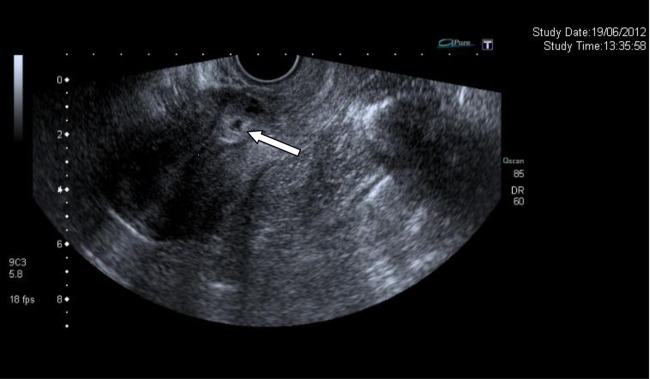

On the third day post-admission, the patient was still bleeding and passing clots per vagina. Therefore, a transvaginal ultrasound scan (TVUS) was carried out, which showed a small gestational sac with a double decidual sac sign without a fetal pole within the anterior myometrium to the site of the scar from the previous caesarean section. It was suggested that she was on her fourth to fifth week of gestation.

On the fourth postadmission day, a second TVUS reported appearances in keeping with the previous scan (see figure 1).

Figure 1.

Transvaginal ultrasound showing an ectopic pregnancy in an old caesarean scar.

This patient was diagnosed with LSCS scar pregnancy.